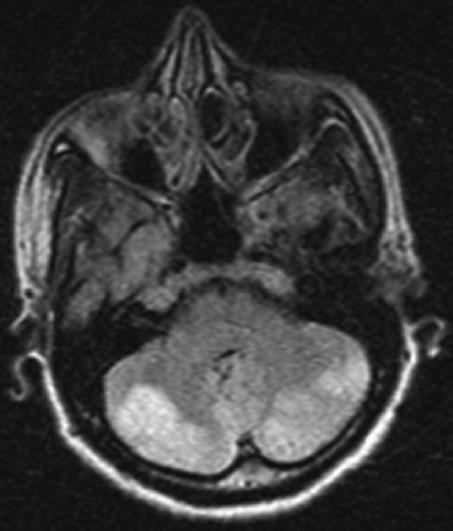

Ischemic stroke following viper bite is rare. We report a case of posterior circulation ischemic infarction following viper bite in a previously healthy woman. Soon after being bitten by the snake on the left leg, she developed local redness, echymosis and one hour later became drowsy. On examination she had skew deviation of eyes and down gaze preference, generalized hypotonia. A CT scan of brain showed infarcts in cerebellar hemispheres and occipital lobes on both sides and that was confirmed on magnetic resonance imaging of brain. Her coagulation profile was deranged. Most common and serious central nervous system complication following snake bite is intracranial hemorrhage. Ischemic stroke commonly involves anterior circulation. Bilateral cerebellar and occipital infraction is not yet reported in literature. Exact cause for the development of infarction is not clear. The possible mechanisms of infarction in this scenario are discussed. Patient was treated with anti-snake venom and showed a good recovery. Early imaging and early treatment with anti-snake venom is important for a favorable outcome.

蝰蛇咬伤后发生缺血性中风较为罕见。我们报告一例既往健康的女性在被蝰蛇咬伤后出现后循环缺血性梗死的病例。在左腿被蛇咬伤后不久,她出现局部发红、瘀斑,一小时后变得嗜睡。检查时,她有眼球斜偏和下视偏好,全身肌张力减退。脑部CT扫描显示双侧小脑半球和枕叶梗死,脑部磁共振成像证实了这一点。她的凝血指标紊乱。蛇咬伤后最常见且严重的中枢神经系统并发症是颅内出血。缺血性中风通常累及前循环。双侧小脑和枕叶梗死在文献中尚未见报道。梗死发生的确切原因尚不清楚。本文讨论了这种情况下梗死发生的可能机制。患者接受了抗蛇毒血清治疗,恢复良好。早期影像学检查和早期使用抗蛇毒血清治疗对于取得良好预后很重要。